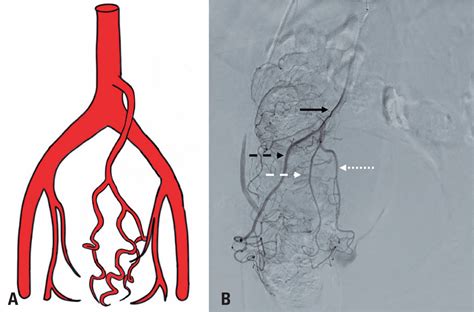

Hemorrhoid Artery Embolization is a cutting-edge, image-guided procedure performed by interventional radiologists. Unlike traditional surgery, which physically removes the hemorrhoidal tissue, HAE works by targeting the blood supply that feeds the hemorrhoids. By reducing the arterial blood flow to the hemorrhoidal plexus, the procedure causes the hemorrhoids to shrink over time, effectively alleviating symptoms like bleeding, pain, and protrusion.

Because it is a minimally invasive technique, it does not require general anesthesia or incisions in the sensitive anal region. Instead, a tiny catheter is guided through a blood vessel in the wrist or groin to the specific arteries supplying the hemorrhoids. Small particles are then injected to block these vessels, successfully reducing the pressure and engorgement of the hemorrhoidal tissues.

2. Guidance: Using real-time X-ray imaging (fluoroscopy), the radiologist navigates a microcatheter through the vascular system.

3. Embolization: Once the specific hemorrhoidal arteries are identified, specialized embolic agents are injected to reduce the blood supply.

• hemorrhoid artery embolization anatomy